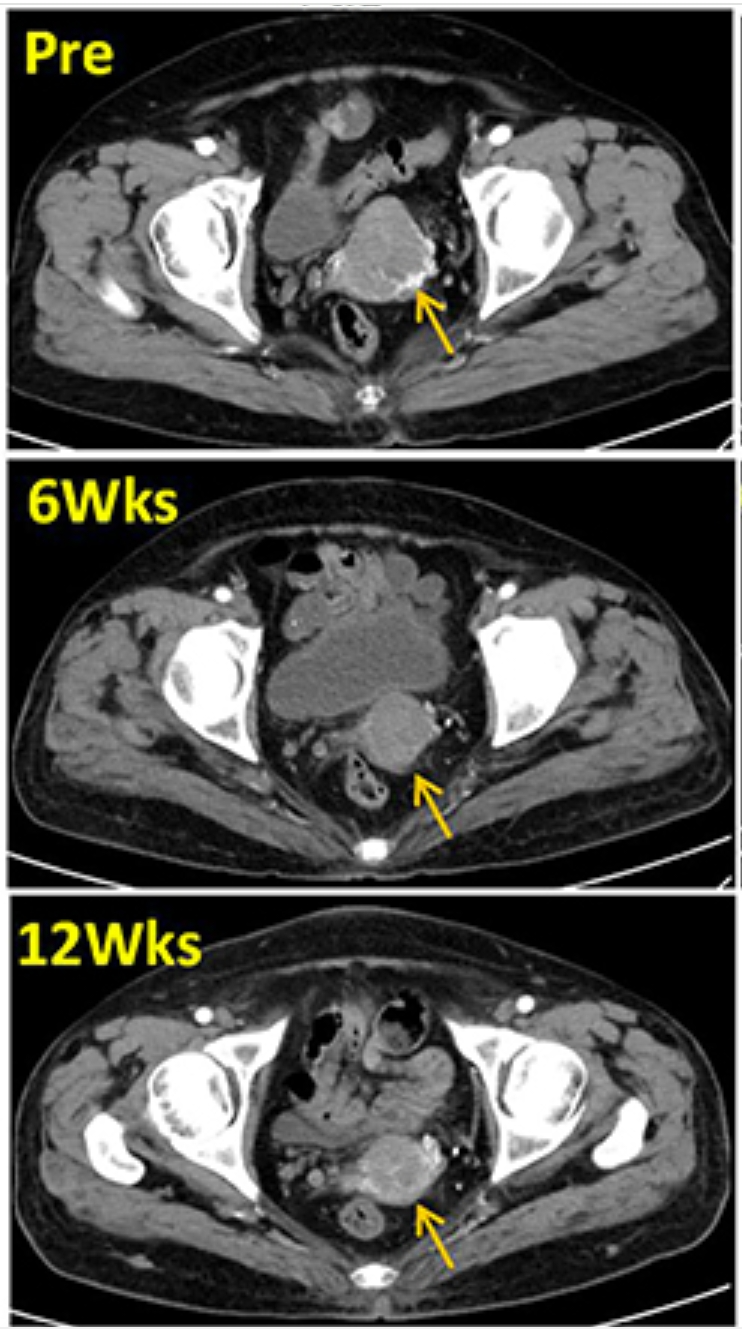

增强盆腔CT:该患者在TIL输注前、治疗后6周和12周时的增强盆腔CT扫描显示,目标病灶分别为4.9cm、3.3cm和3.0cm,显然治疗后患者肿瘤迅速缩小,详见图1。

图1 TIL治疗前后,增强盆腔CT对比